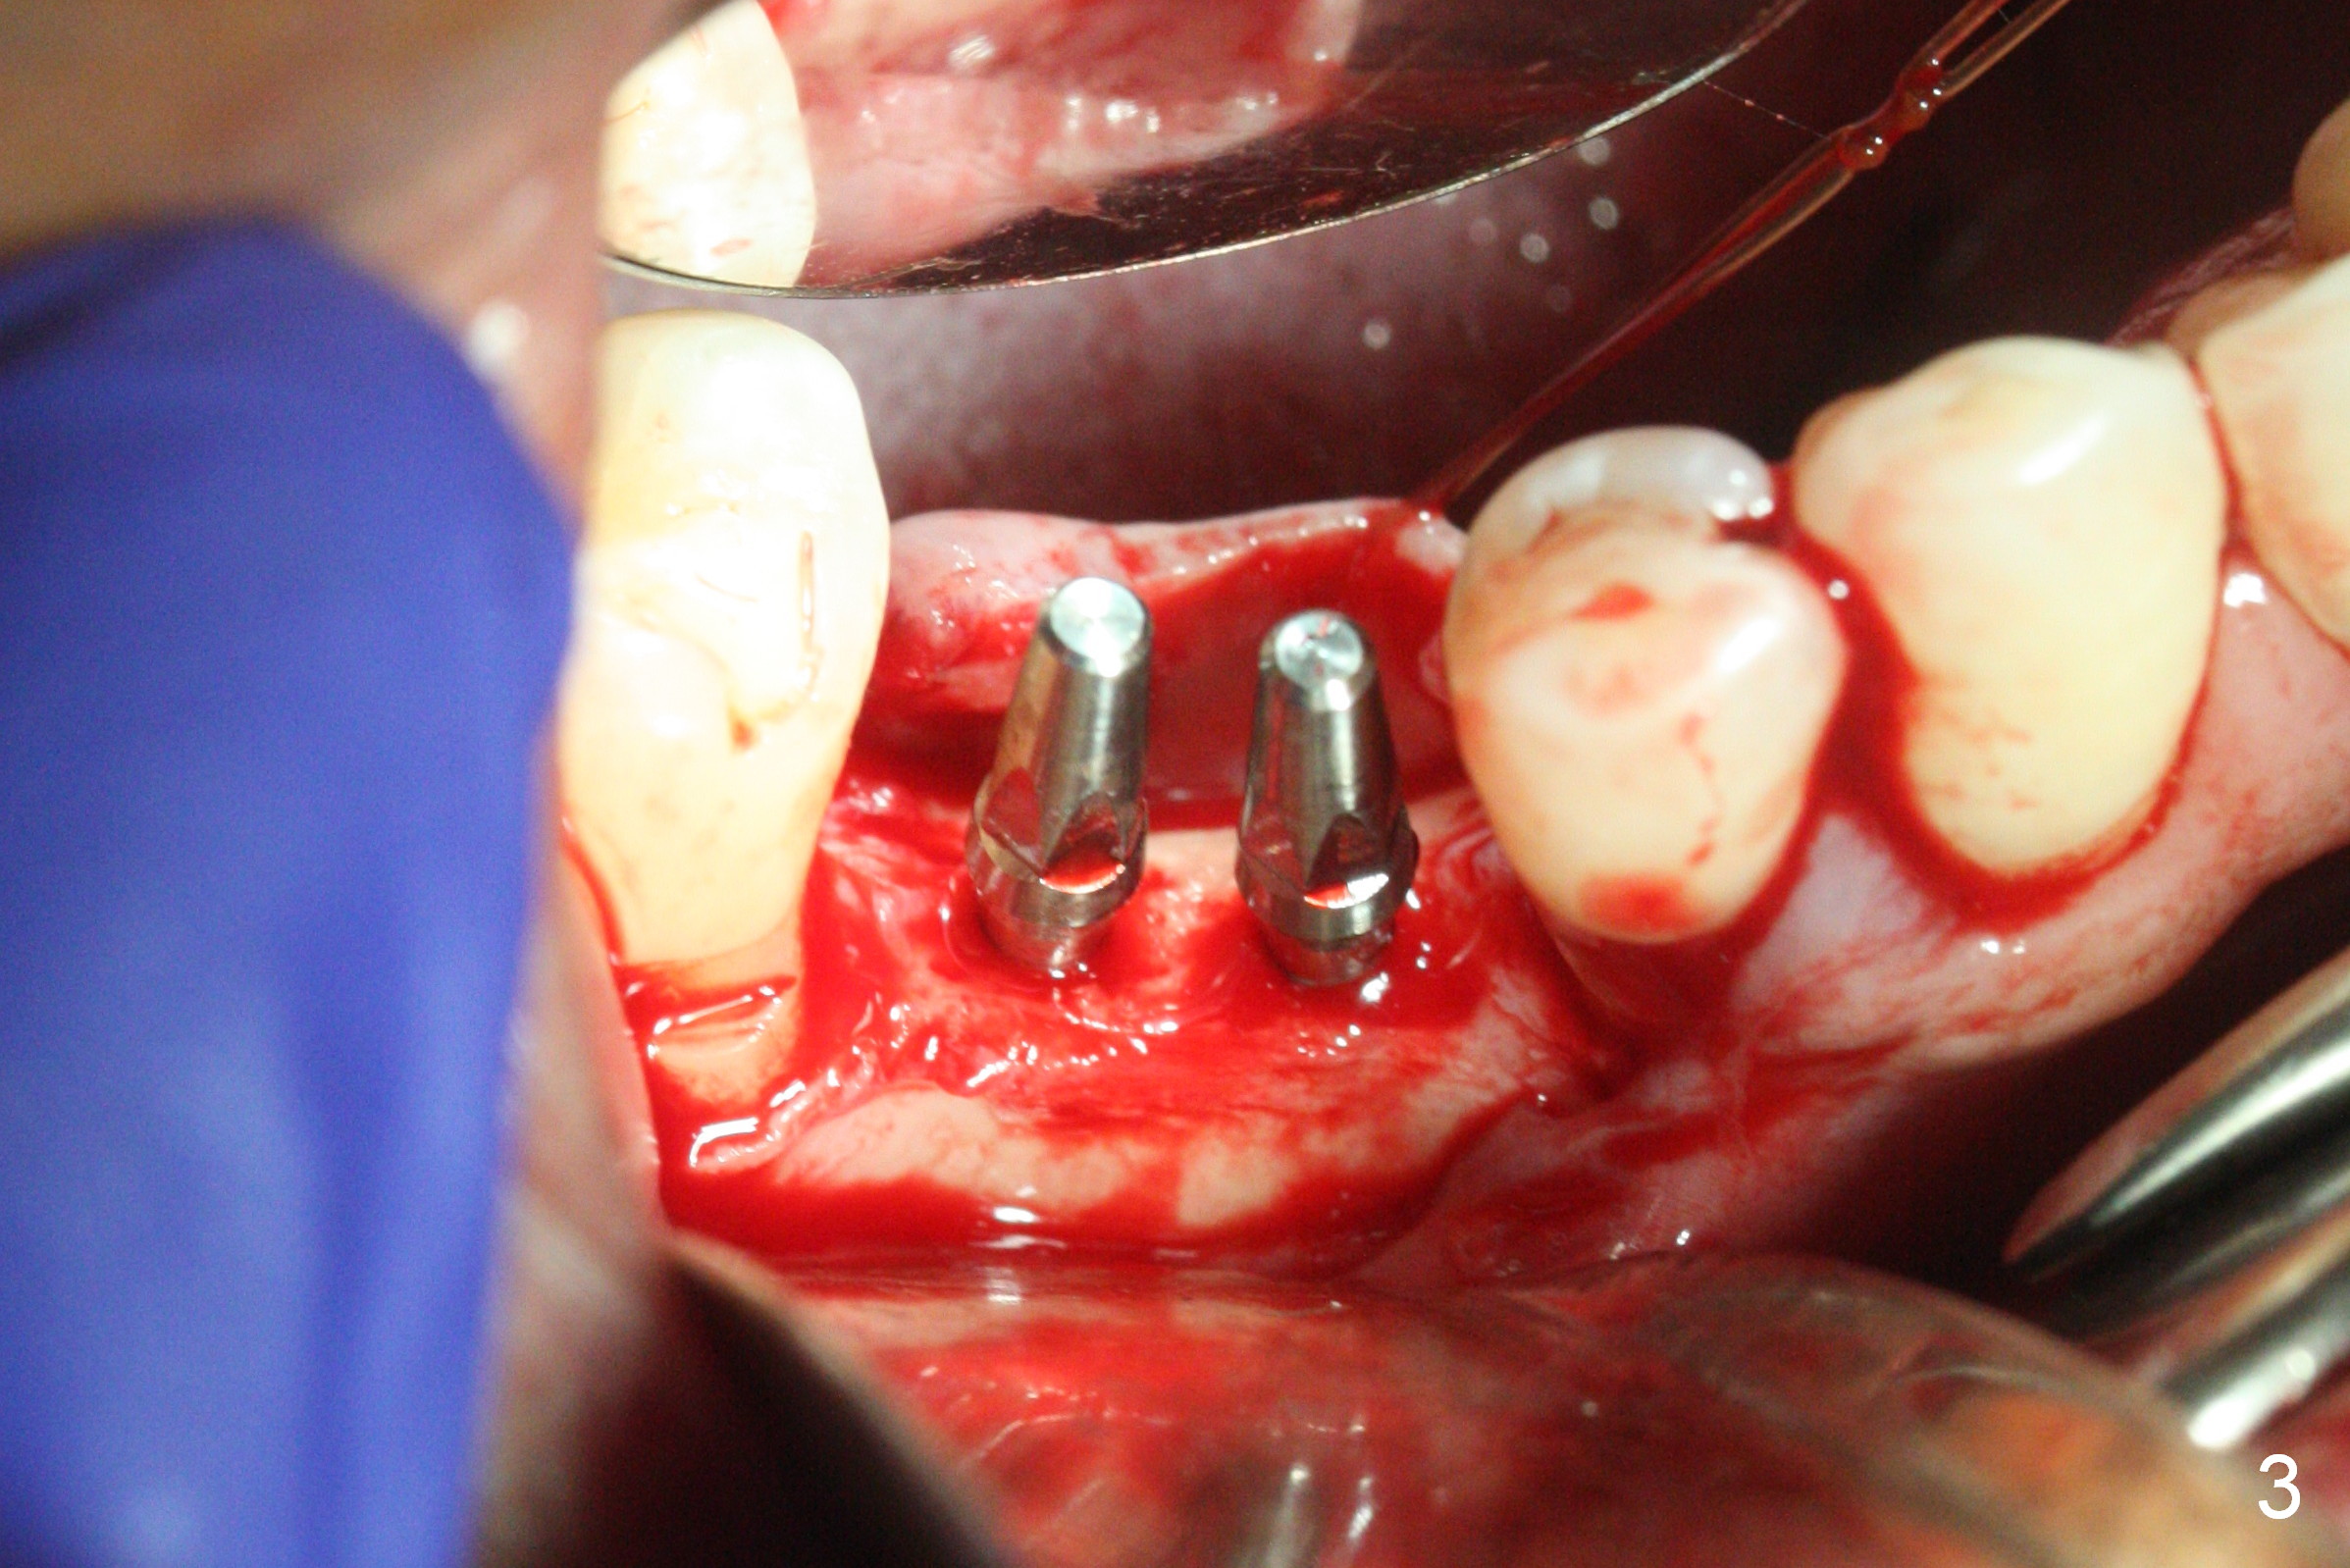

The wide mesiodistal space at #29 is most likely due to congenital missing permanent tooth (i.e., deciduous molar retention before extraction 34 years ago). The patient is now 62 years old. In fact the buccolingual width is not so narrow (Fig.1). After incision, the ridge is approximately 5 mm. Two osteotomies are established with 1.2 mm drill at 8 mm mesially and 1.5 mm one at 10 mm distally (Fig.2). The apparent approximation of the mesial osteotomy to the Mental Loop (red dashed line) is related to X-ray angulation, since there is 1-2 mm separation when two of 2x10(2) mm 1-piece implants are placed (Fig.3,4). Insertion torques of the mesial and distal implants are less than 25 and 15 Ncm, respectively. In fact bone graft is placed around the distolingual root of the tooth #30 after calculus removal (Fig.4 <). Following reduction of the abutments, periodontal dressing is applied locally. The dressing dislodged 13 days postop (Fig.5). A provisional is going to be fabricated 4 weeks postop when the wound heals (Fig.6). No bone loss is observed 4 months postop (Fig.7).